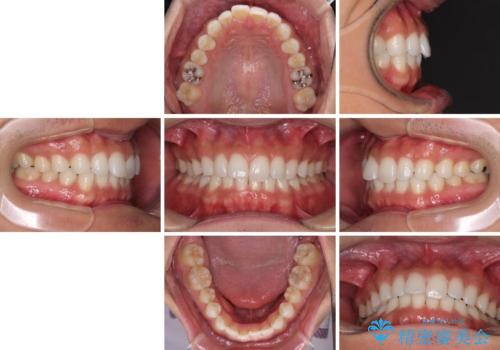

- 上下前歯のデコボコを気にして来院された患者様です。

以前矯正をした後戻りということで、歯列不正はそれほど大きくなかったため、インビザライン・ライトを用いて矯正治療を行うこととしました。

1日22時間以上しっかりと装着してくださったので、半年かからずに治療を終えることができました。